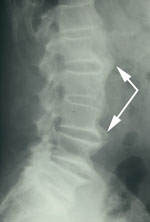

DISH is Diffuse Idiopathic Skeletal Hyperostosis.

DISH generally affects at least 2 or more levels of the spine, and most often, 97% of cases, affects the thoracic spine.